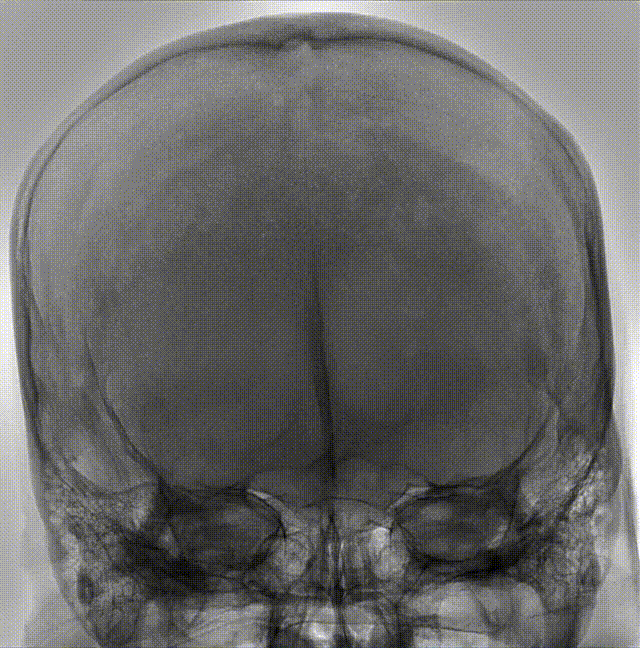

术前造影

术后检查